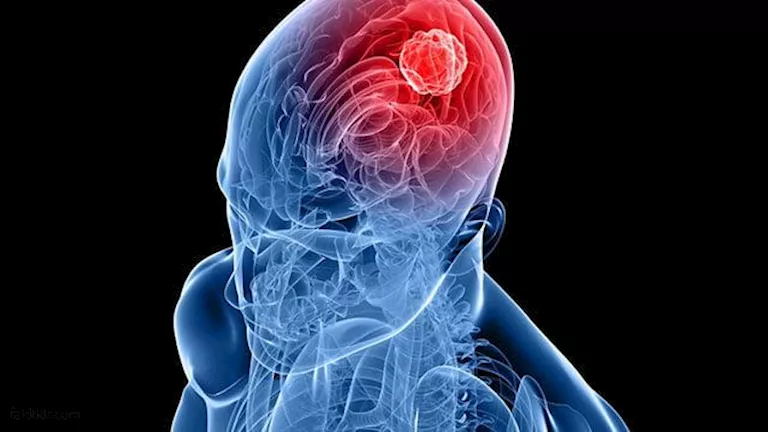

غالبًا ما تظهر أورام الدماغ دون أن تكتشف حتى تصل إلى مرحلة خطيرة، ولا يزال تشخيصها من أصعب الحالات، ويعود ذلك أساسًا إلى عدم تحديد أعراضها وعدم وضوحها، لذا فإن فهم سبب عدم اكتشاف الأورام حتى مراحلها المتأخرة والتعرف على علاماتها التحذيرية الأولية يمكن أن ينقذ حياة المرضى بشكل كبير.

تتميز أورام الدماغ بأعراض مثل الغثيان غير المبرر، والصداع المتكرر، والدوار، والنوبات، وفقدان التوازن، وضعف البصر، وتغيرات في أنماط الكلام، بالإضافة إلى تغيرات معرفية وسلوكية أخرى، هذه العلامات غير محددة، وقد تعزى إلى التوتر، أو التقلبات الهرمونية، أو التغيرات البيئية، أو عوامل نمط الحياة مثل قلة النوم، وهذا غالبًا ما يدفع الناس إلى تجاهلها كعلامات تحذير مبكرة لحالة طبية خطيرة، بحسب timesofindia.

أعراض ورم الدماغ تتطور تدريجيًا، أي أنها تتفاقم مع مرور الوقت، لذلك، لا تُكتشف إلا عندما يصبح الألم لا يطاق، في كثير من الحالات، تنمو الأورام ببطء، ما يسمح للدماغ بالتكيف مع الألم والتعايش معه، تختلف الأعراض أيضًا باختلاف حجم الورم وموقعه في الدماغ، أحيانًا، تبقى الأعراض مخفية حتى يتوسع الورم بما يكفي لإحداث تغييرات ملحوظة.